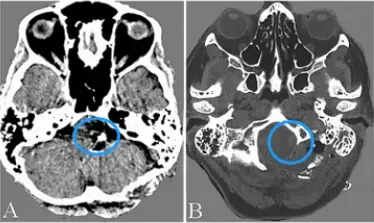

85岁妇女在一次预防性脑MRI评估中被诊断为左无症状性后交通动脉瘤。她有高血压和轻微肺气肿的病史。血管造影显示一个12毫米直径的动脉瘤起源于后交通动脉(图3a)。

由于她的年龄,医生建议她进行随访。然而,在随后的2年里,动脉瘤的直径扩大到30mm,并用含有的血栓物质压迫脑干和丘脑(图3b)。入院前5个月,临床症状发展为右侧偏瘫和左侧动眼神经麻痹。意识水平在入院前1个月下降,完全卧床不起。

当MRI显示动脉瘤病灶直径达到35mm时,转到川岛明次教授所在医院进行手术治疗(图3c)。

图3(a-c):(a)诊断4个月后的血管造影显示动脉瘤直径为12毫米,起源于后交通动脉。(b)诊断2年3个月后磁共振成像显示动脉瘤内有血栓,直径达30mm,压迫脑干。(c&d)在磁共振成像(c)和三维ct血管造影上,病灶直径扩大到35mm。6个月后(d)动脉瘤从后交通动脉向上扩张。右侧大脑后动脉未见。